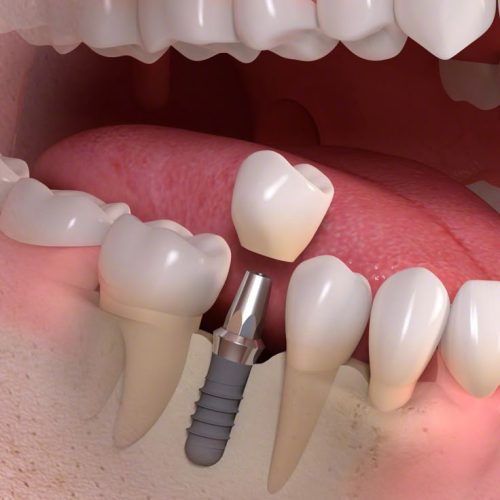

Dr Nitesh Rai, specializes in replacement of teeth with complete dentures, removable partial dentures, fixed partial dentures and Implants.

He has been actively involved in providing implant treatment for over two decades. He is also a committed academician, educating dental students and has been associated with Krishnadevaraya college of Dental sciences, Bengaluru as a Senior Professor, PG Guide and teacher in the Department of Prosthodontics, Crown and Bridge and Implant.

He is really a humble person and well-qualified in his profession. My experience was amazing. He explained the issue and solutions and also gave me sometime to think on the procedure. I underwent the implant procedure, which was remarkably pain free. After 3 months the teeth was placed . Thanks to his precise digital measurements and meticulous attention in detail . Today , I have a prefect crown in place . I am grateful to Dr Nitesh Rai for his exceptional skill and compassion , for restoring not just my smile but my confidence too.

Wonderful experience! I had multiple implants placed and the treatment was smooth and painless. Dr. Nitesh Rai explained every step and gave me full confidence. Today I can bite into apples and enjoy food like before. The clinic staff are warm and friendly – it feels like home.

Yashoda Dental is truly the best for implants. I was nervous initially, but Dr. Nitesh Rai’s care and personal attention made everything easy. My implants feel natural and I can eat ever